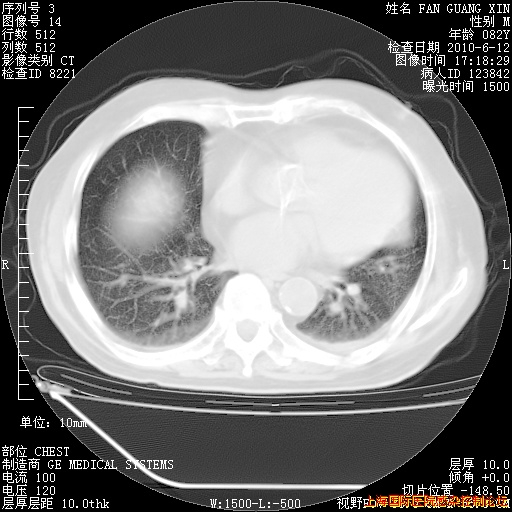

6月12日肺窗

整整相隔30天的肺部CT好像有所好转啊。甲强龙减量第3天,需要观察体温。

海管,自昨日你和我通完话后,不知您岳父消化道症状有无缓解?体温怎样?阅读7.12日胸部ct,个人认为目前激素治疗是有效的,甲强龙减量是适宜的。因在抗痨治疗,需密切观察肝功、肾功能和血常规。不过,老年、长期住院和大量使用激素,很担心菌群失调发生